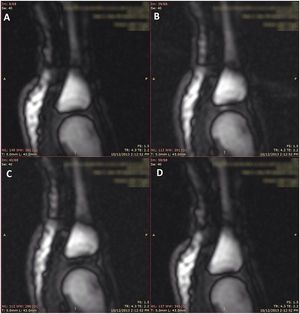

Cracking sounds emitted from human synovial joints have been attributed historically to the sudden collapse of a cavitation bubble formed as articular surfaces are separated. Unfortunately, bubble collapse as the source of joint cracking is inconsistent with many physical phenomena that define the joint cracking phenomenon. Kawchuk et al. (2015) support the view that tribonucleation is the process which governs joint cracking. This process is characterized by rapid separation of surfaces with subsequent cavity formation, not bubble collapse as has been the prevailing viewpoint for more than a half century. Observed previously in vitro, this work provides the first in-vivo demonstration of tribonucleation on a macroscopic scale and as such, provides a new theoretical framework to investigate health outcomes associated with joint cracking. This framework will allow scientists to compare and contrast this process against tribonucleation observed between inanimate surfaces, an approach that may reveal how joint cracking affects cartilaginous joint surfaces. Presently, the literature in this area is confusing in that the energy produced during joint cracking is though to exceed the threshold for damage, but habitual knuckle cracking has not been shown to increase joint degeneration. Ultimately, by defining the process underlying joint cracking, its therapeutic benefits, or possible harms, may be better understood.